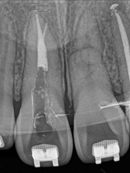

Root Canal Cases